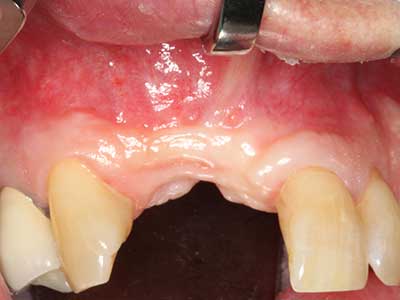

Die Präparation des lateralen Fensters bei der externen Sinusbodenelevation stellt gerade für chirurgisch unerfahrene Implantologen eine große Herausforderung dar. Die knöcherne Bedeckung der Kieferhöhle ohne eine Verletzung der darunterliegenden Schneider’schen Membran abzutragen ist dabei nur ein Teil der Operation – nach Schaffung eines ausreichenden Zugangs muss die Kieferhöhlenschleimhaut vorsichtig mobilisiert werden, um Raum für das einzubringende Material bzw. die Implantate zu schaffen. In dieser Indikation ist die Piezochirurgie zweierlei hilfreich: zum einen kann durch Verwendung diamantierter Instrumente eine selektive Knochenabtragung erfolgen und die darunter liegende Schleimhaut bleibt bei vorsichtiger Vorgehensweise intakt. Zum anderen unterstützen die Ultraschallfrequenzen zusätzlich eine komplikationslose Ablösung der Schleimhaut – sie werden durch spezielle stumpfe Ansätze in den Spaltraum zwischen Schleimhaut und Kieferhöhlenboden übertragen (Cassetta, Ricci et al. 2012, Pereira, Gealh et al. 2014) (Rickert, Vissink et al. 2013). So erscheint es nicht verwunderlich, dass in aktuellen Übersichtsarbeiten über die externe Sinusbodenelevation neben der Verwendung von rauen Implantatoberflächen und dem Einsatz von Knochenersatzmaterialien auch der Einsatz von piezoelektronischen Geräten als positiv bewertet wird (Wallace, Tarnow et al. 2012).

Bilder klinischer Anwendungsfälle